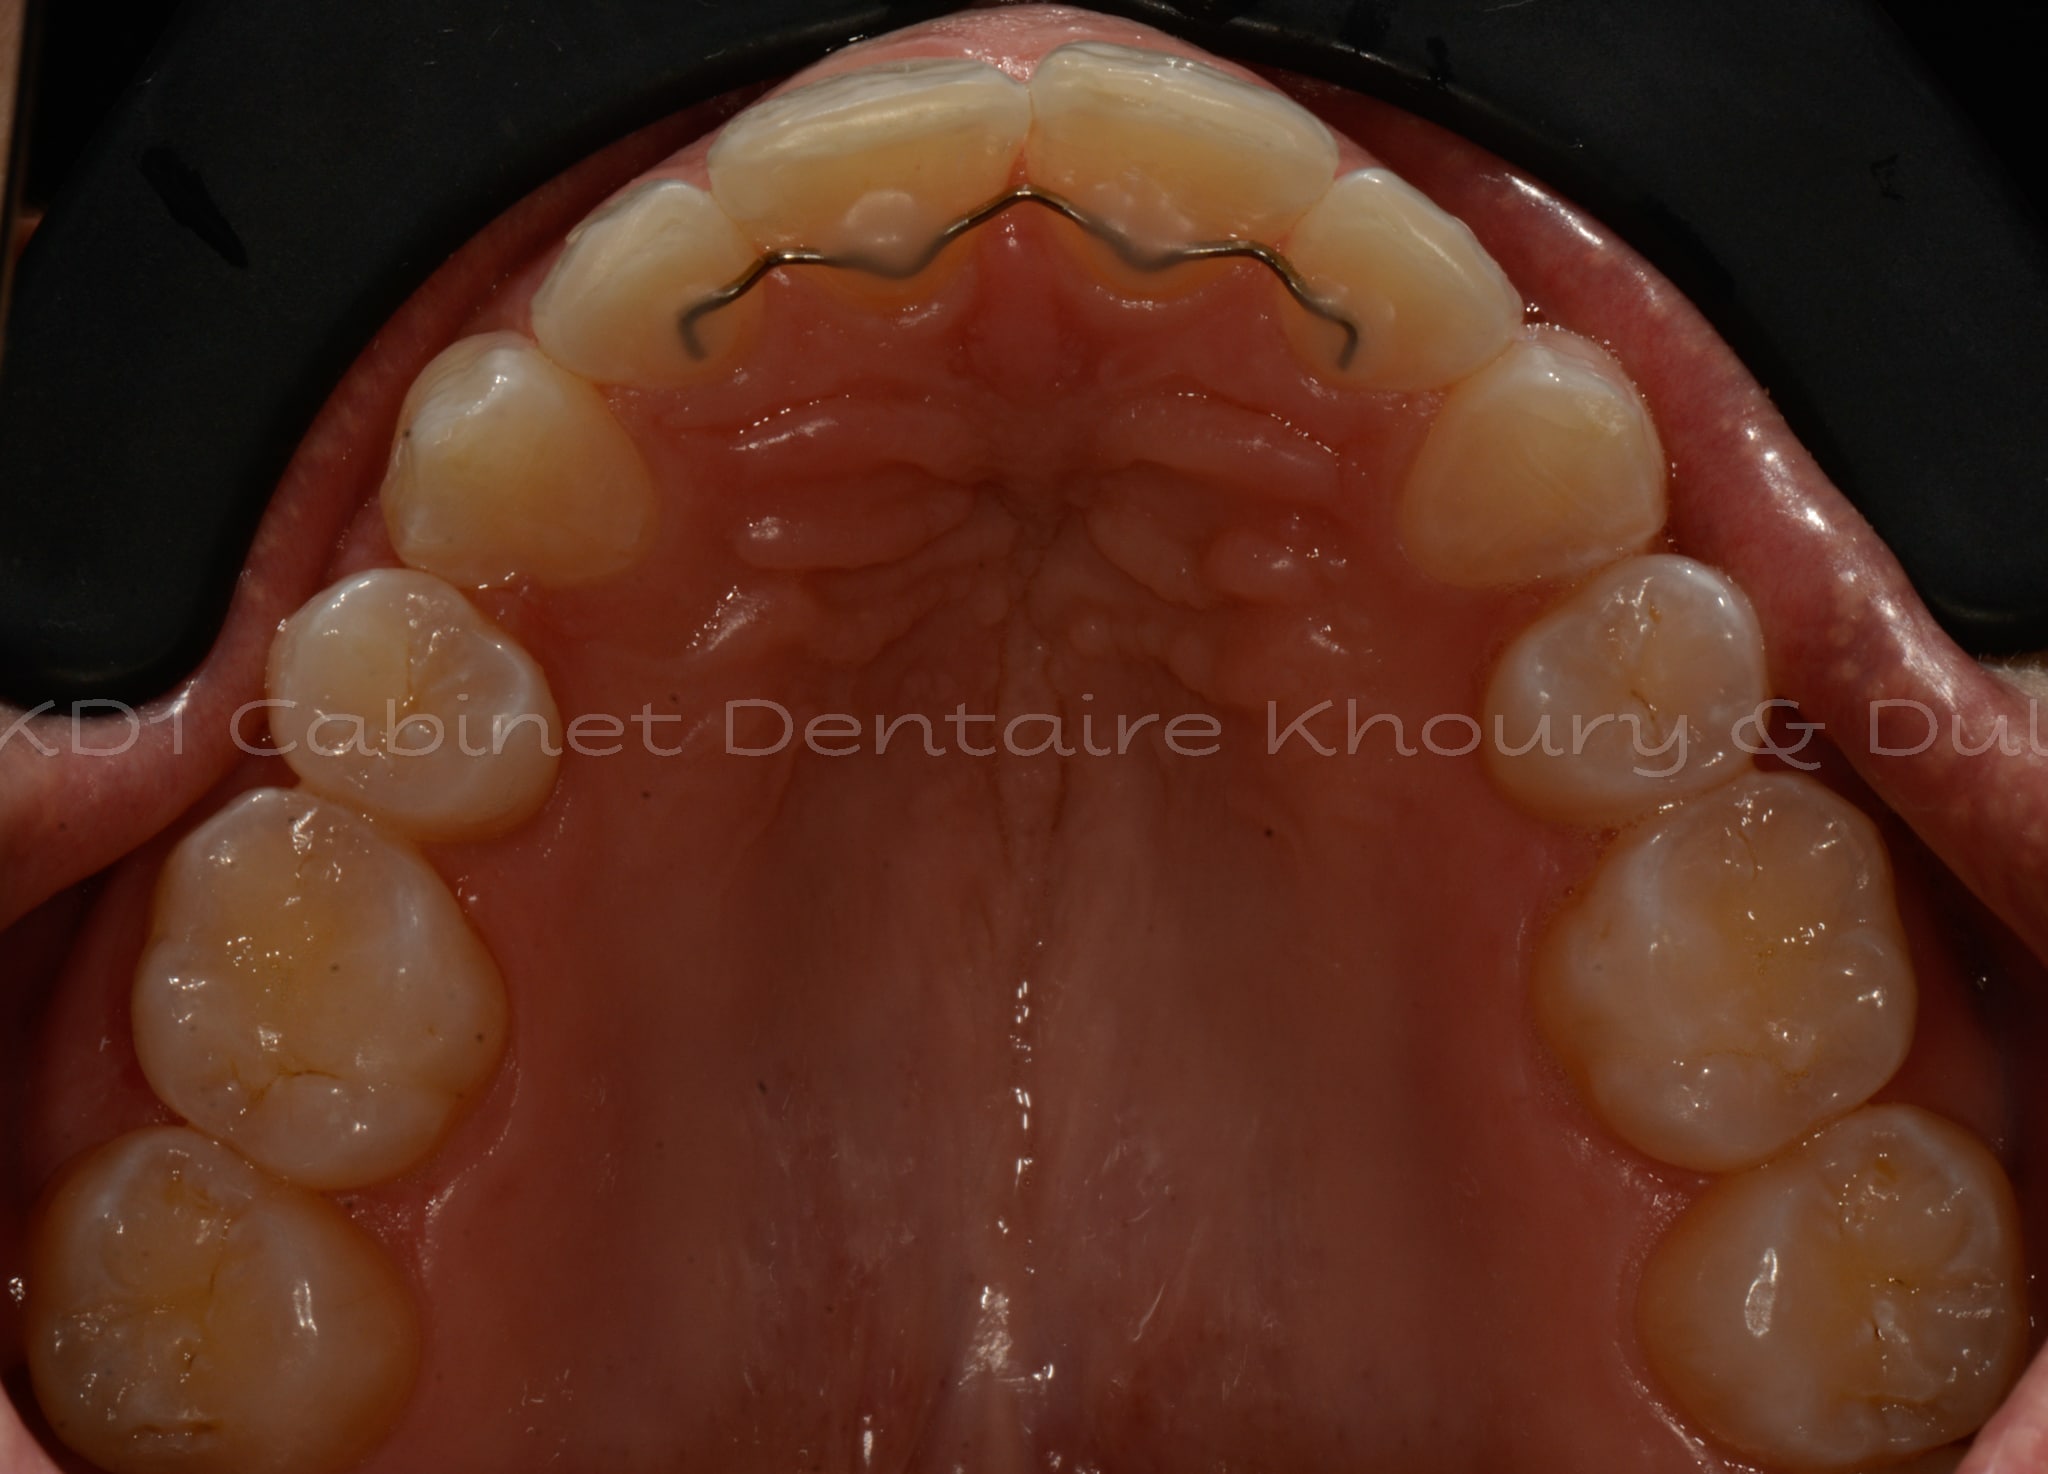

Cas #1 – Traitement avec des bagues, deuxièmes prémolaires et dent de sagesse supérieures ectopiques.